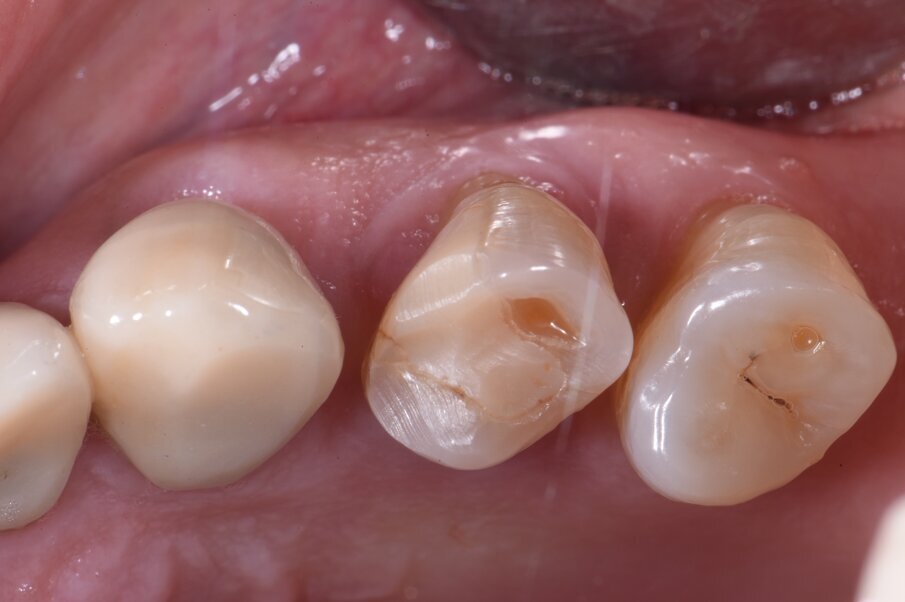

Per ridurre la perdita volumetrica dei tessuti perimplantari, alcuni studi clinici5-7 hanno riportato l’utilizzo delle cappette di guarigione customizzate avvitate sugli impianti immediatamente inseriti negli alveoli post-estrattivi. In questo case report viene descritta l’applicazione delle cappette di guarigione customizzate seguendo la procedure Cad-Cam in un flusso di lavoro digitale. Prima di eseguire l’estrazione si procede con il rilevamento dell’impronta digitale per copiare l’anatomia del profilo d’emergenza del dente. A questo punto si estrae in modo molto conservativo il dente. Si posiziona l’impianto dentale senza inserimento dei biomateriali nel void creato fra la superficie dell’impianto e la parete dell’alveolo. Si avvita una cappetta eseguita con la procedura Cad-Cam copiando l’anatomia del dente estratto (Figg. 1a, 2).

Tre mesi dopo, l’inserimento dell’impianto i volumi anatomici dei tessuti perimplantari presentano la stessa forma e dimensione di quella precedente dell’estrazione del dente (Fig. 3). Dopo il rilevamento dell’impronta digitale si disegnano i margini gengivali del manufatto protesico, prestando attenzione al profilo d’emergenza (Figg. 4a, 4b). La corona in disilicato di litio viene cementata rispettando i profili anatomici conservati dalla cappetta castomizzata (Fig. 5). A distanza di due anni si possono notare il mantenimento volumetrico delle strutture tessutali attorno al restauro implant-protesico.